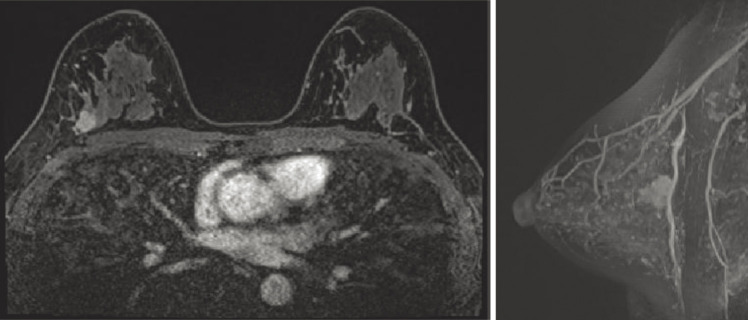

Case presentation: We describe the case of a 44-year-old female patient with invasive ductal carcinoma of the right breast. Cobblestone papillomatosis was present in the gingiva. She had a medical history of bilateral adenomatous goiters for 10 years. Her mother had been diagnosed with breast cancer, thyroid and tongue tumors, gastric polyps, hepatic hemangioma, and collagen disease. Additionally, the patient's maternal grandmother had a history of colon cancer. Based on the patient's family history and physical findings, CS was suspected, and direct DNA sequencing analysis revealed a haplotype c.634del mutation in exon 7 of the PTEN gene. Although there is no clear evidence supporting risk-reducing surgery for PHTS, a right nipple-sparing mastectomy, sentinel lymph node biopsy, and tissue expander reconstruction were performed.